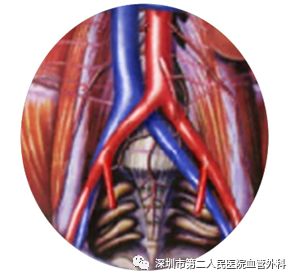

三、血栓为什么好发于下肢深静脉,且多发于左侧

静脉的血流速度远小于动脉,因此,静脉血栓的发病率要远远高于动脉。在静脉系统中,血液回流的主要阻力是血液本身的重量,而下肢处于人体的最低处,向上回流时所需克服的重力就最大,血栓当然就易发。之所以左下肢更多发,是由于左髂静脉前面被右髂动脉跨越、压迫(图4),后面又是坚硬的脊柱,形成一个天然的狭窄,因此,左下肢的血液回流更难些,因此更易发生血栓。

图4 左髂静脉被右髂动脉跨越压迫